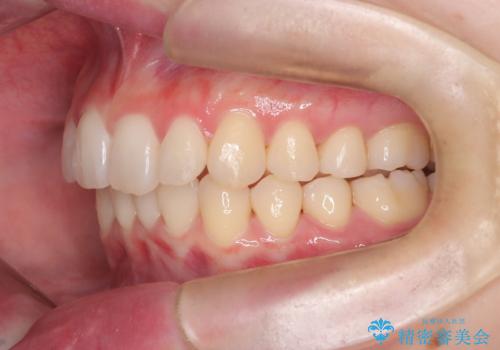

インビザライン矯正|下顎前歯1本抜歯でスムーズに歯列改善(1年で完了)

- 患者様は、下顎前歯のガタつきを改善したいとのことで来院されました。診察の結果、スペース不足により前歯が重なっている状態でした。抜歯をせずに並べると前歯が前方に突出してしまうため、下顎の前歯を1本抜歯し、インビザラインで矯正する治療計画を立てました。できる限り追加のアライナーを使用せずに治療を完了できるよう、初回の治療計画を慎重に設計しました。

下顎前歯を1本抜歯し、歯列のスペースを確保。その後、インビザラインを用いて計画通りに歯を移動させ、噛み合わせも整えました。患者様の協力もあり、ゴムかけなどを適切に行い、予定通り1年で治療を完了。追加アライナーを使用することなく、計画通りに治療を終えることができました。患者様からは「思ったより早く終わり、仕上がりにも満足している」と喜びの声をいただきました。